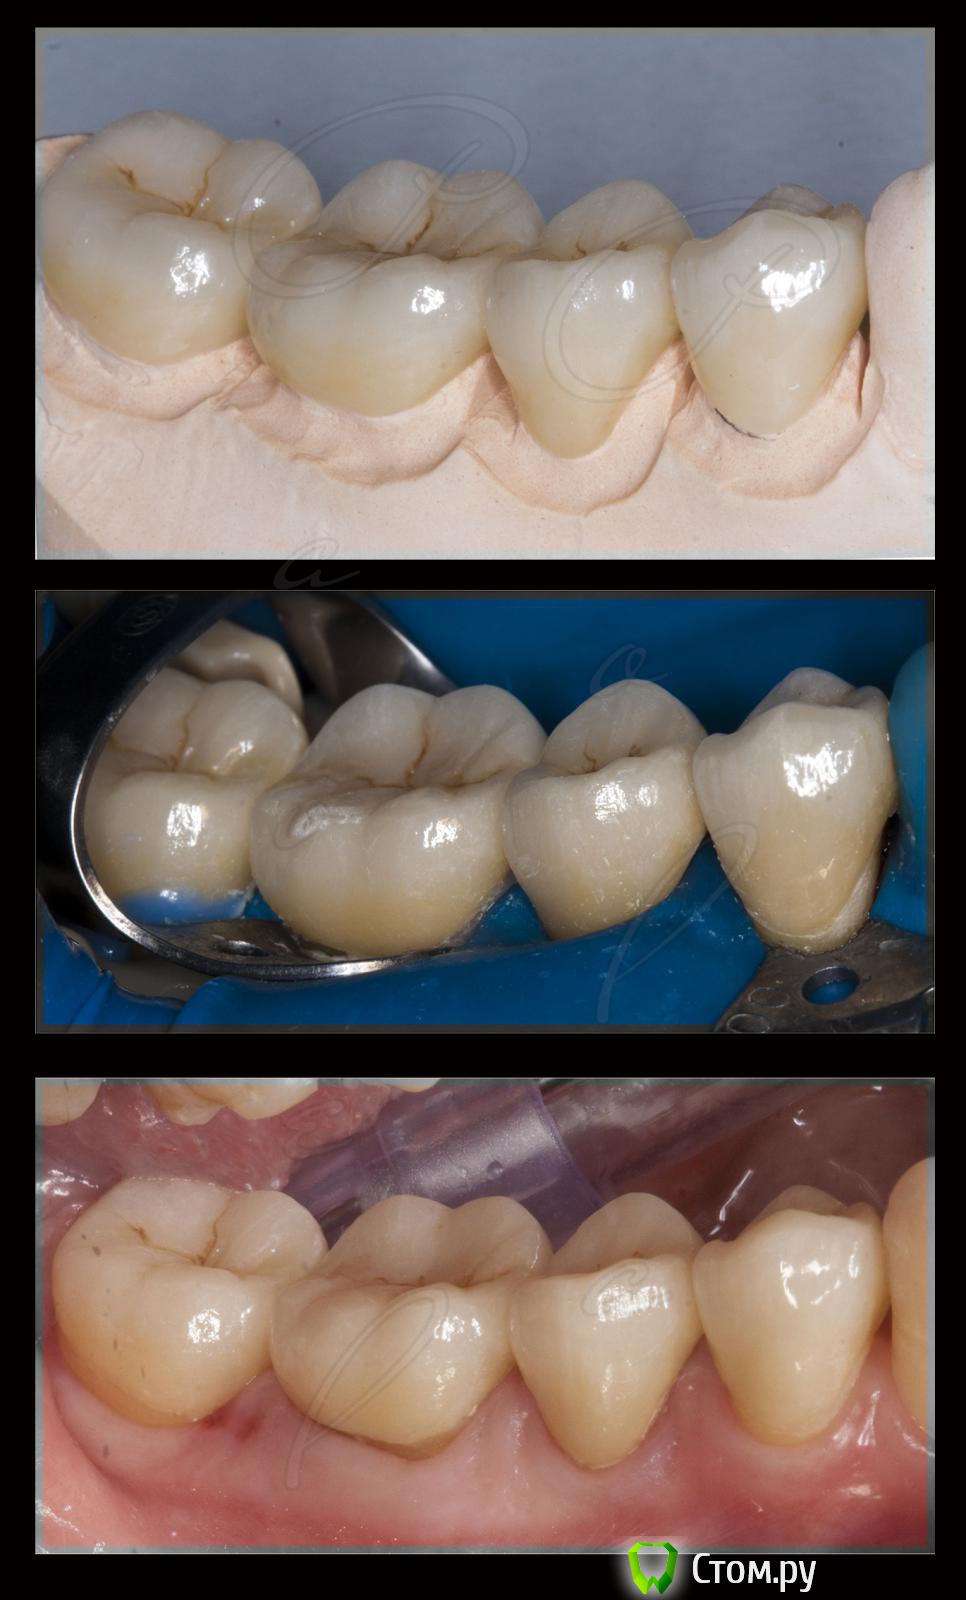

M@estro Опубликовано 14 сентября, 2014 Поделиться Опубликовано 14 сентября, 2014 (изменено) Эндо - ортопедический кейс. До вмешательства : http://s020.radikal.ru/i715/1409/ab/12f0b8206958.jpg 44 : http://s019.radikal.ru/i606/1409/ec/a20e5f3456a6.jpg в два этапа,язычный канал был обтурирован во второе посещение. Этот кейс был опубликован в группе "перелечивания и эндо". Латеральная конденсация. 45 : http://i077.radikal.ru/1409/ae/46e0381ae7eb.jpg Была положительная симптоматика ( перкуссия) , после лечения исчезла. "Patency" не получил. 46 : http://s018.radikal.ru/i520/1409/1a/57ad2b5a48aa.jpg тут стандартная "добыча" . 4.7 витальный. Ортопедия : http://s50.radikal.ru/i129/1409/b5/916fdb8a0ede.jpg http://s019.radikal.ru/i642/1409/82/4c4871c06c06.jpg http://s018.radikal.ru/i523/1409/76/4b62878e182a.jpg Такие дела . Изменено 14 сентября, 2014 пользователем M@estro 14 Ссылка на комментарий